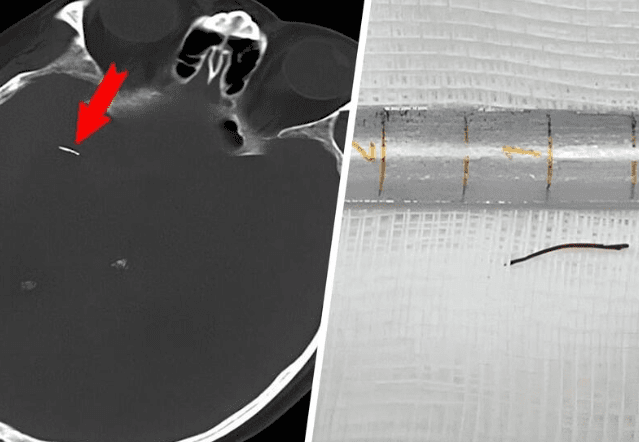

Как пишет Газета.ru, 74-летний пациент из провинции Сычуань обратился к врачам из-за проблем с памятью. Медики обнаружили, что в артерии головного мозга мужчины застряла очень маленькая игла. Она спровоцировала кровотечение (псевдоаневризму), что и стало причиной симптомов.

Родные мужчины вспомнили, что 20 лет назад он проходил процедуры иглоукалывания из-за мигрени. Врачи считают, что именно тогда игла могла попасть в артерию за глазом.

Чтобы удалить иглу, врачи вырезали часть черепа пациента. Для ее извлечения понадобился хирургический микроскоп. Поврежденный иглой сосуд закрыли с помощью маленького металлического зажима. Через десять дней после операции мужчину отключили от аппарата искусственной вентиляции легких, он пошел на поправку. Однако из-за осложнения во время общей анестезии у пациента развилась летальная инфекция легких, и он прожил лишь три недели после операции.